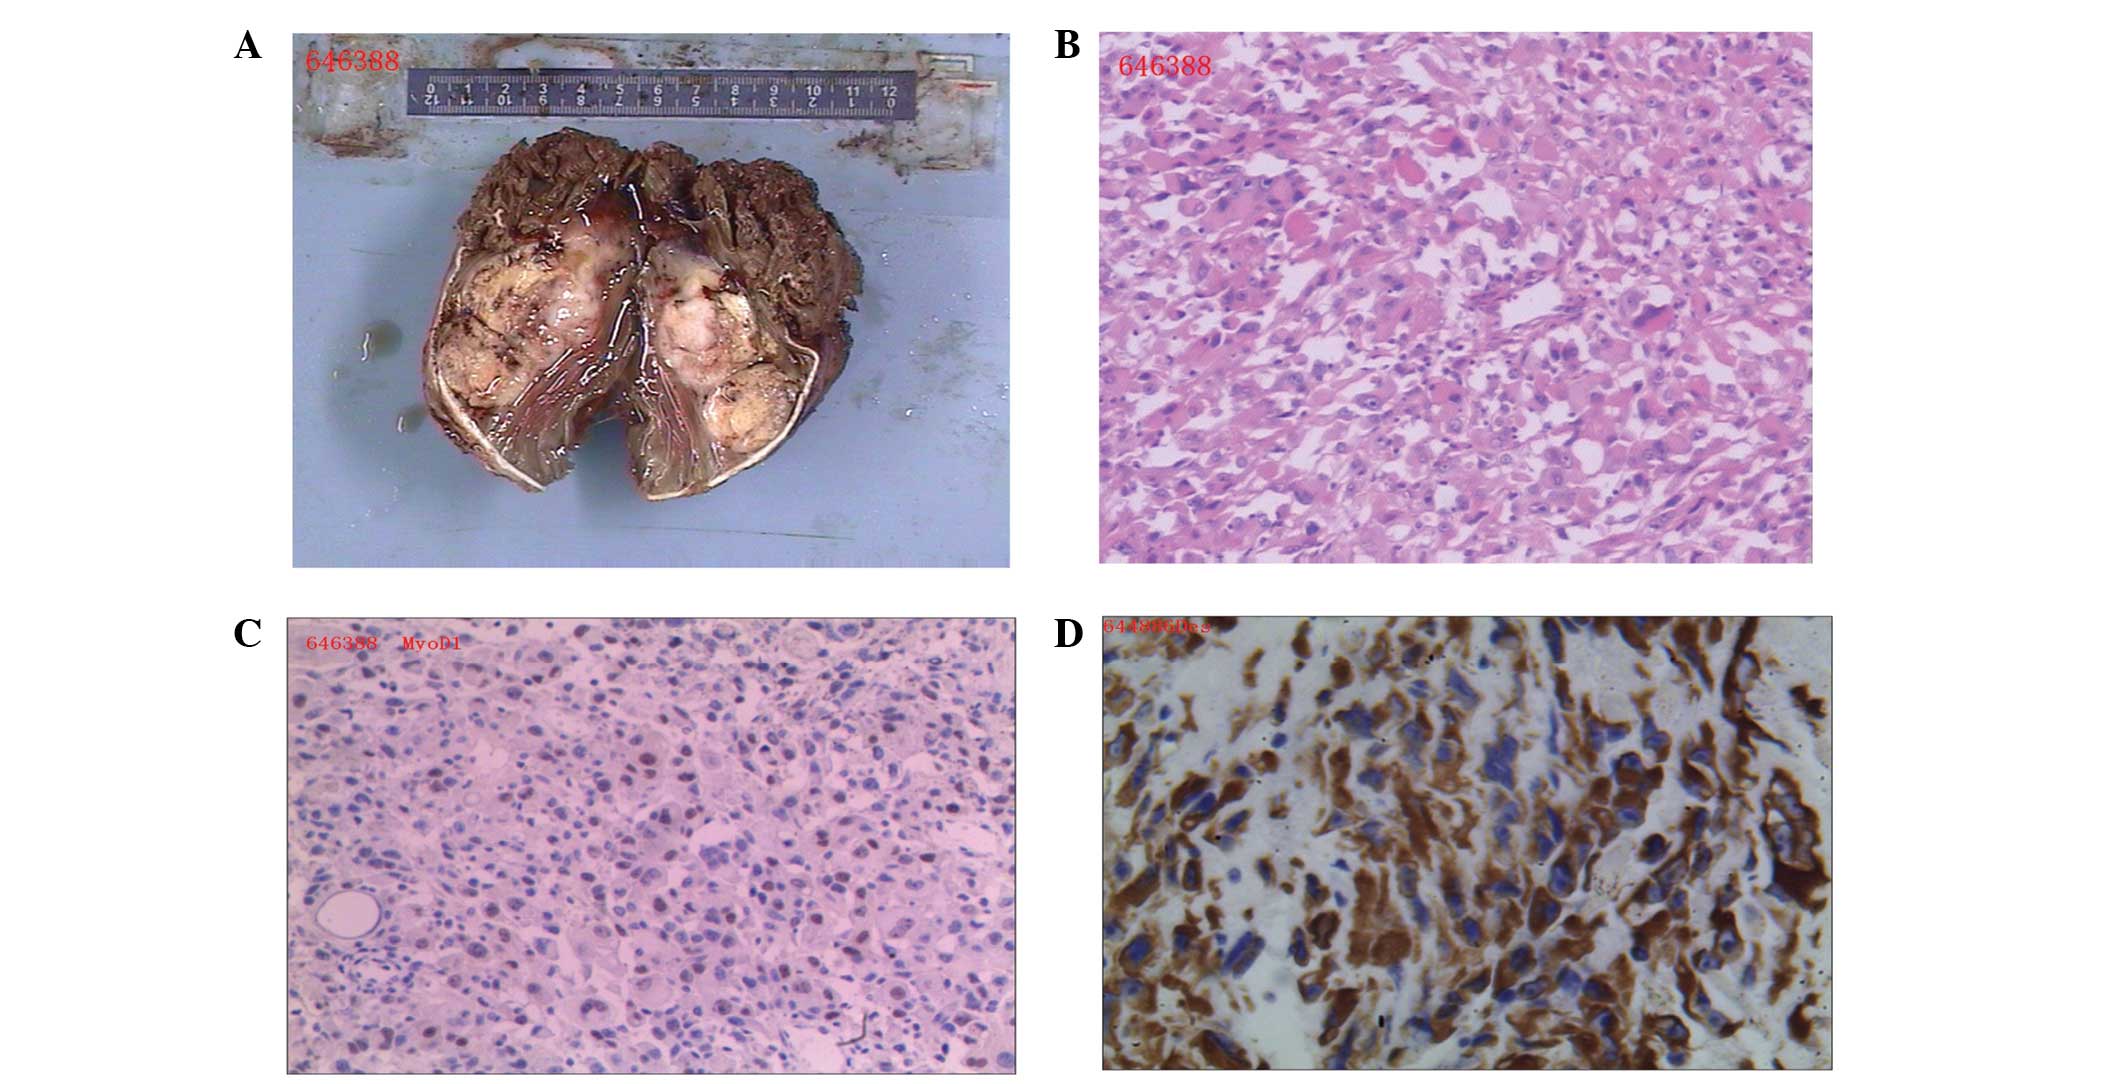

Misdiagnosis Of Primary Pleomorphic Rhabdomyosarcoma Of The Right Thigh

www.spandidos-publications.com

www.spandidos-publications.com

rhabdomyosarcoma pleomorphic thigh case examination gross misdiagnosis primary adult young right report figure ol